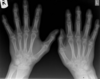

**Psoriatic arthropathy** Pencil in cup X-ray showing some of changes in seen in psoriatic arthropathy. Note that the DIPs are predominately affected, rather than the MCPs and PIPs as would be seen with rheumatoid. Extensive juxta-articular periostitis is seen in the DIPs but the changes have not yet progressed to the classic 'pencil-in-cup' changes that are often seen.

**Gout of MTP** Soft tissue swelling in early disease Periarticular erosions ‘punched out lesions’ in late disease Normal joint space

Arthritis hands: compare osteoarthritis, rheumatoid arthritis and psoriatic arthritis

Psoriatic arthritis